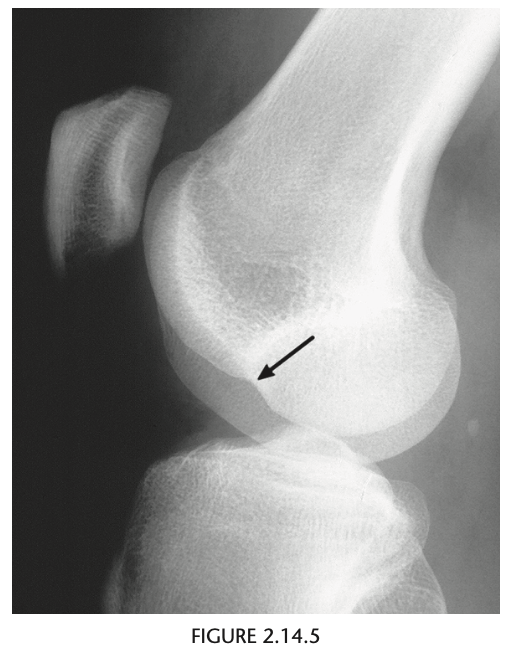

Conventional radiographic findings of an ACL

tear include avulsion fractures from the femoral or

tibial attachment of the ACL (Fig. 2.14.4, arrow), the

Segond fracture (Fig. 2.14.4, arrowhead), or a deep

lateral sulcus sign (Fig. 2.14.5, arrow).